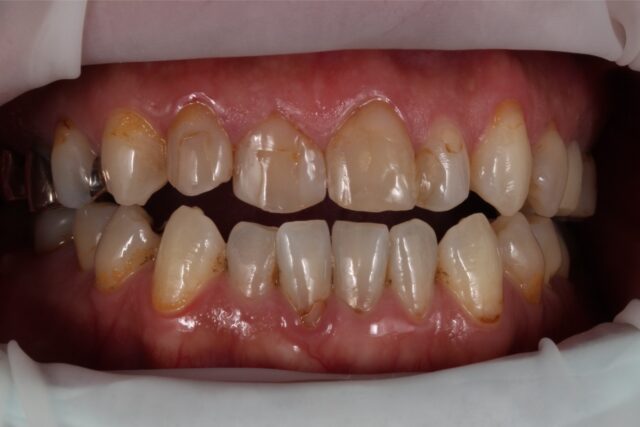

矯正なしで開咬を改善したケース

| 症状 | 元々開口傾向があり、前歯での咬合が十分に機能していない状態でした。 その後の治療を経て、前歯での咬合が困難となったため、機能改善を目的に治療へ |

| 治療法 | 右上4〜左上4(計8本)ダイレクトボンディング |

| 費用 | 約70万 |

| 通院回数 | 合計4回(週1程度) |

| 備考 | 費用面及び残存歯質の温存を考慮し、矯正治療や補綴処置ではなく、ダイレクトボンディングによる対応を選択した。 |